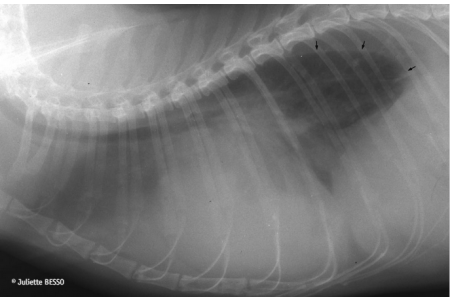

Forty cats with pleural effusion (22 cardiac and 18 non-cardiac) were studied. NT-proBNP concentrations in plasma and pleural fluid were strongly correlated. Plasma (P